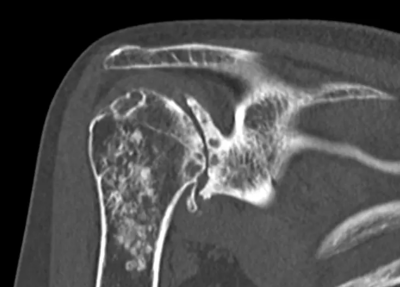

Coronal CT

A deeply concave glenoid

The glenoid at the time of surgery. It is shaped like a bowl.

Normally, the baseplate is fixed to the glenoid with screws.

If the glenoid is deformed, the shape of the baseplate may not fit the glenoid properly.

Therefore, a shaped allograft is attached to the baseplate to fit the deformed glenoid.

The baseplate with the allograft is fixed to the glenoid.

The glenosphere is attached.